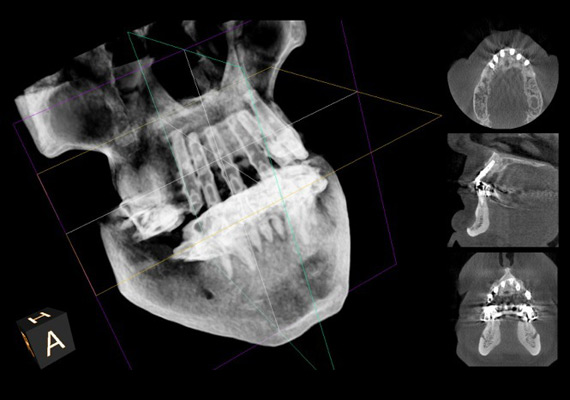

La 3D Radiology: an Essential Technology

3D radiology has significant diagnostic advantages and enables extraordinary surgical planning and precision.

For implantology, it helps determine bone graft requirements and the optimal choice of implants. It provides a complete view of the sinuses and the inferior alveolar nerve.

During wisdom tooth extractions, this technology helps to accurately identify the trajectory of the nerve that gives feeling to the chin and the lip and minimizes the risk of prolonged numbness following the extractions.